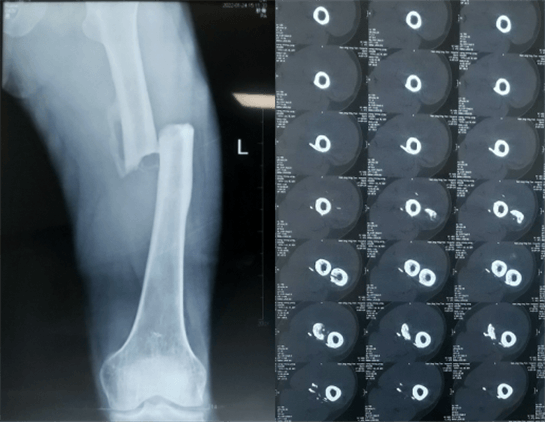

患者:男性,43歲,左股骨干骨折髓內(nèi)釘內(nèi)固定術(shù)

醫(yī)院:南京應(yīng)天骨科醫(yī)院

股骨是下肢的主要負重骨,有其特殊的解剖關(guān)系,周圍肌肉發(fā)達,因此一旦股骨干骨折后如果治療不當,容易造成肌肉牽拉,導(dǎo)致畸形和功能障礙。治療股骨干骨折,必須遵循恢復(fù)肢體的長度及力線,無旋轉(zhuǎn),盡量行以微創(chuàng),保護骨折局部血運,促進愈合。髓內(nèi)釘對骨折的固定能夠達到較大的穩(wěn)定性和堅固性,可以減少醫(yī)源性污染,減少軟組織分離及周圍血供破壞,有利于骨折早期愈合,是治療股骨干骨折的首要治療方法。

術(shù)前檢查